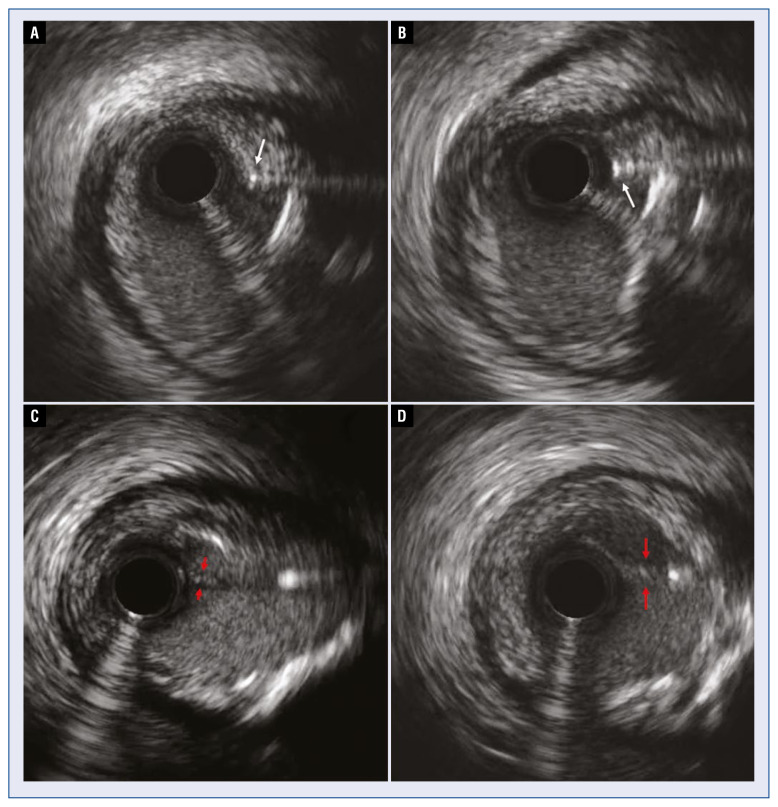

背景:本研究的目的是描述内膜下移位(SIS)的机制,标准化诊断标准,并使介入治疗界对这一现象更加敏感。慢性全闭塞(CTO)的经皮冠状动脉介入治疗(PCI)是复杂的分岔病变累及CTO段或其邻近。在CTO PCI时冠状动脉内装置的斑块外扩张可以通过内内侧皮瓣将剥离平面扩展到分叉上,从而导致相应的侧支或主支受压。本文首次描述这种现象,并将其命名为内膜下移位。方法:来自3个国际CTO PCI高容量中心的经验丰富的CTO操作员回顾性检索其个人记录中的典型SIS病例,总结关键特征并提出诊断标准。结果:本组病例共7例,CTO PCI行血管内显像(2例)或间接血管造影征象(5例)。5例由支架扩张引起,1例由球囊膨胀引起,1例因血管造影警示信号而流产。在4例中,SIS导致分支完全闭塞,无论何时尝试球囊都难以膨胀。4例需要紧急救助干预,2例左支闭塞,导致心脏指标升高。结论:内膜下移位是CTO分支值得注意的并发症,可能导致相关侧甚至主分支闭塞。建议在支架植入前进行冠状动脉内成像以了解组织平面。这种现象的一些违反直觉的特性,比如它对气球的耐火性,必须由CTO操作员了解才能有效解决。

Background: The aim of this study was to describe the mechanism of subintimal shift (SIS), standardise diagnostic criteria and sensitise the interventional community to this phenomenon. The treatment of chronic total occlusions (CTO) by means of percutaneous coronary intervention (PCI) is complicated by bifurcation lesions involved in the CTO segment or adjacent to it. Extraplaque expansion of intracoronary devices during CTO PCI may extend the dissection plane over the bifurcation with the consequential side or main branch compression by an intimo-medial flap. This phenomenon is hereby described for the first time and named subintimal shift.

Results: The series comprised 7 demonstrative cases, illustrating SIS by intravascular imaging (2 cases) or indirect angiographic signs during CTO PCI (5 cases). Five cases were triggered by stent expansion, 1 by balloon inflation and 1 case was aborted after angiographic warning signs. In 4 cases, SIS resulted in total occlusion of a branch, refractory to ballooning whenever attempted. Four cases required bailout intervention and in 2 cases the branch was left occluded, resulting in a rise of cardiac markers.

Conclusions: Subintimal shift is a noteworthy complication in CTO bifurcations, potentially resulting in occlusion of the relevant side or even the main branch. Intracoronary imaging prior to stenting is recommended to understand the tissue planes. Some counterintuitive peculiarities of this phenomenon, like its refractoriness to ballooning, must be known by CTO operators for its efficient resolution.